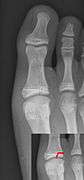

Salter–Harris fracture images

| Salter–Harris fracture radiographs with insets showing fracture lines. | ||||||||